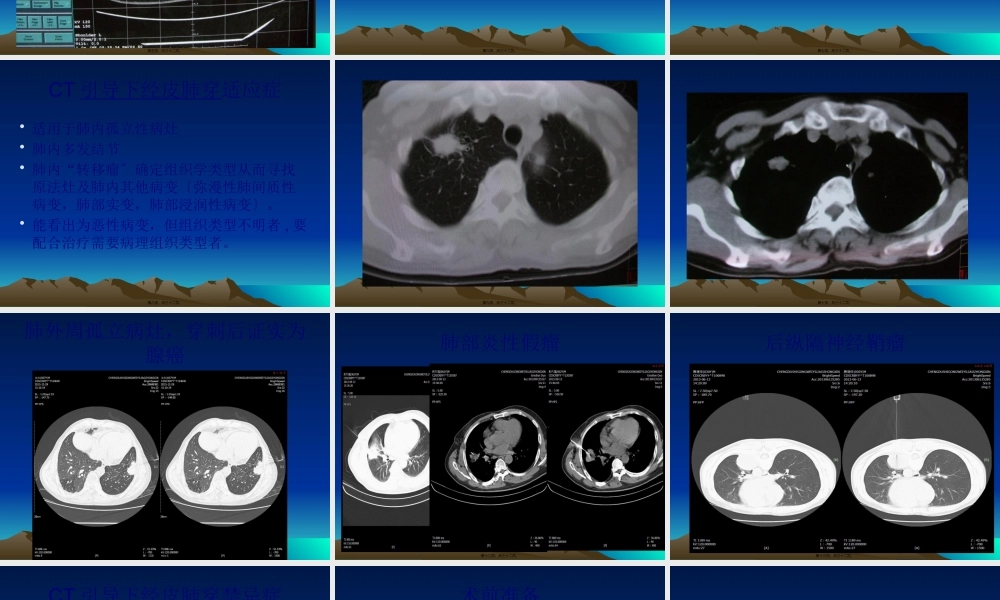

CT引导下经皮肺穿刺活检放射科赵果城第一页,共三十二页。•概述:CT经皮肺穿是呼吸系统疾病确诊的重要方法,是在CT引导下,利用细针经皮对肺部肿块进行穿刺、活检,吸取该部位一定量的组织进行检查,以获得其病变的定性诊断的一项介入诊断方法。第二页,共三十二页。设备和器械•CT机:目前运用三代以上的CT机均可•穿刺针:依据病灶大小选择,14-18G为粗针,粗针口径较大,获取组织多,损伤大;21-23G为细针,口径小,损伤小,但所获组织少。依据其作用又分抽吸(千叶针,GREEN针),切割(TRUCUT针,活检枪)•定位器械:以前用栅格定位尺,现多数螺旋CT均有定位线.第三页,共三十二页。CT机定位线第四页,共三十二页。第五页,共三十二页。CT引导下经皮肺穿国内外开展现状•CT引导下经皮肺穿是20世纪70年代影像医学的重大开展,自1976年Haaga和Alfidi首次成功地进行了CT导向经皮针活检,使针活检的准确率和适用范围大为提高,过去以透视导向难以进行活检的部位,如肺门旁和纵隔部也可行经皮针活检。1982年Lindgren首次报道自动活检枪系统,进一步提高了活检取材的成功率。1996年实时CT透视系统试用于临床,从而使经皮针活检进展至以现代影像技术为导向手段的、适用范围广泛、高度准确的介入诊疗技术,在肺部疾病诊断和治疗中发挥越来越大的作用。第六页,共三十二页。CT引导下经皮肺穿目的•一些经病史、影象学检查、痰脱落细胞、纤维支气管镜等各项检查均不能确诊的胸部病变,通过活检取得细胞学、组织学资料可作出定性的诊断,对于治疗方案的选择、制定以及治疗后随访、预测预后等方面均具有重要作用。第七页,共三十二页。CT引导下经皮肺穿适应症•适用于肺内孤立性病灶•肺内多发结节•肺内“转移瘤〞确定组织学类型从而寻找原法灶及肺内其他病变〔弥漫性肺间质性病变,肺部实变,肺部浸润性病变〕。•能看出为恶性病变,但组织类型不明者,要配合治疗需要病理组织类型者。第八页,共三十二页。第九页,共三十二页。第十页,共三十二页。肺外周孤立病灶,穿刺后证实为腺癌第十一页,共三十二页。肺部炎性假瘤第十二页,共三十二页。后纵隔神经鞘瘤第十三页,共三十二页。CT引导下经皮肺穿禁忌症•重症肺气肿,患者呼吸功能严重减退•肺心病,肺动脉高压•咳嗽不能控制,不能控制呼吸,不合作•设计的穿刺道上有肺大泡,囊肿性病变,针活检有可能致气胸•肺内病变疑为包虫病或血管性病变•凝血功能障碍,不能纠正者•肺内,胸腔内,纵隔内化脓性病变第十四页,共三十二页...

2、本站所有内容均由合作方或网友上传,本站不对文档的完整性、权威性及其观点立场正确性做任何保证或承诺!文档内容仅供研究参考,付费前请自行鉴别。